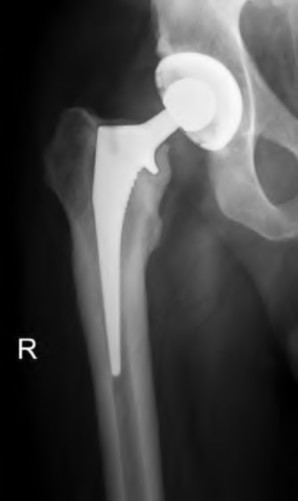

Question 51

A patient requires a femoral revision THA for aseptic loosening. Radiographs demonstrate extensive metaphyseal bone loss with the diaphyseal cortical bone remaining fully intact for only 3 cm distal to the tip of the current stem. According to the Paprosky femoral defect classification, what type of defect is present?

Radiographs of a failed THA demonstrate severe periprosthetic osteolysis. The acetabular component has migrated 4 cm superiorly and 2 cm medially past Kohler's line, and the radiographic teardrop is completely destroyed. Which Paprosky acetabular defect is present?

Explanation